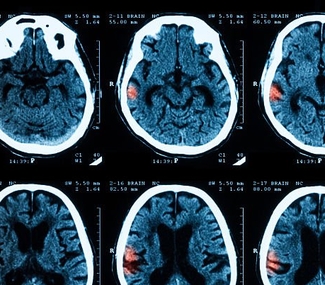

МРТ – это метод нейровизуализации, который позволяет получить детальное изображение структуры мозга. МРТ используется для выявления возможных структурных причин эпилепсии, таких как опухоли, сосудистые мальформации, атрофия гиппокампа, кортикальные дисплазии или рубцовые изменения. Результаты МРТ могут помочь определить тип эпилепсии и планировать хирургическое лечение, если оно необходимо.